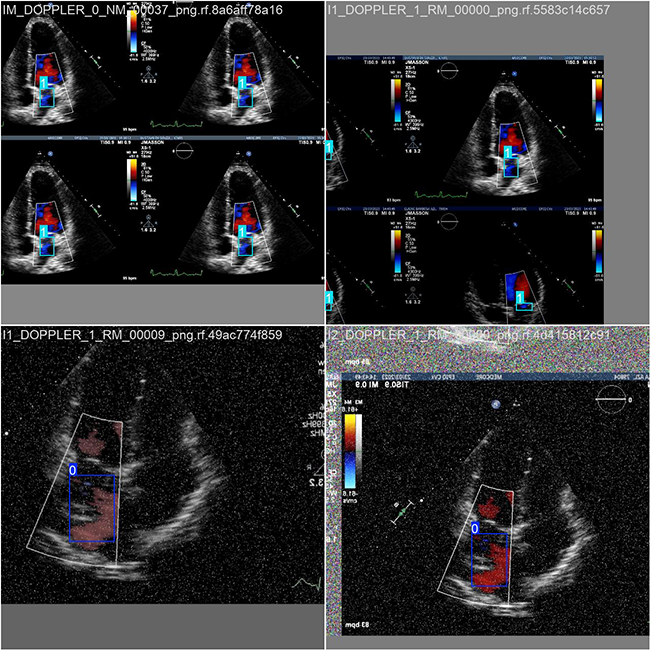

本研究基于涉及心脏右心室医学影像分析的相关数据集,并利用Labelimg标注工具精确标记每张图像中的目标边界框(Bounding Box)及其对应分类信息。在此数据集上训练YOLOv8n模型,并对其性能表现进行系统性评估与对比分析。该流程涵盖以下环节:数据准备阶段、模型训练阶段以及模型评估阶段。本次标注的主要类别集中在上述领域中,并共收录了1834张图像样本的具体分布情况如下

训练集包含1283张图像,并被用于模型的训练与优化过程。

验证数据集包含367张图片,并被用来评估模型面对未曾见过的数据时的表现,并以此来防止过拟合问题。

测试数据集则包含了184张图片,并被用作综合性能测试以全面检验模型的泛化能力。

部分数据集图像如下图所示:

部分标注如下图所示:

该种数据分布策略通过确保各阶段的数据平衡实现了模型训练过程中的均匀性分配,并为YOLOv8n模型的开发与性能评估提供了可靠的技术支撑